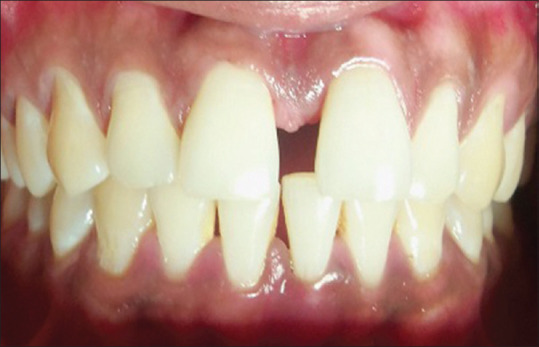

Materials and methods: A study included 100 subjects divided into four groups. Group I: stable coronary artery disease with chronic periodontitis, Group II: stable coronary artery disease without chronic periodontitis, Group III: chronic periodontitis without coronary artery disease, and Group IV: healthy controls. Gingival index, Russell's periodontal index, pocket depth, and clinical attachment level were recorded. Venous blood was collected from the patients, and serum fibrinogen, CRP, and lipid profile levels were estimated.